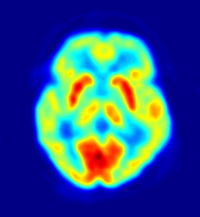

وتمكن تقنيتان جديدتان مأمونتان هما: التصوير المقطعي المغناطيسي بابتعاث البوزيترونات والتصوير بالرنين المغنطيسي الوظيفي، العلماء من دراسة الدماغ السليم أثناء عمله. ولاتتطلب هاتان التقنيتان اتصالاً مباشرًا بالدماغ، ولكنهما ينتجان صورًا شبيهة بصور الأشعة السينية، والتي توضح أي أجزاء الدماغ يعمل أثناء أداء الشخص نشاطًا ذهنيًا أو بدنيًا، حيث يوضح التصوير المقطعي بابتعاث البوزيترونات أجزاء الدماغ الأكثر استهلاكًا للجلوكوز، بينما يوضح التصوير بالرنين المغنطيسي الوظيفي، الأجزاء التي يشير فيها استهلاك معدلات عالية من الأكسجين إلى نشاط الجزء.

في أواخر القرن التاسع عشر، لاحظ العلماء أن تدمير جزء معين من الدماغ، يسبب نفس العجز اللغوي في معظم المرضى. فالتدمير الذي يصيب الفص الجبهي الأيسر في منطقة بروكا، والتي سميت على اسم الجراح الفرنسي بيير باول بروكا، يدمر بدوره القدرة على الكلام، بينما يسبب التدمير الذي يلحق بالفص الصدغي الأيسر، في منطقة فيرنك، التي سميت على اسم عالم الأعصاب الألماني كارل فيرنك، صعوبات في فهم اللغة. وقد قادت هذه الملاحظات العلماء إلى الاعتقاد بأن الدماغ يعالج الكلمات في مراحل منظمة، عبر سلسلة من المناطق ذات الصلة باللغة. ولكن باستخدام تقنيات تصوير معينة، مثل التصوير المقطعي بابتعاث البوزيترونات والتصوير بالرنين المغنطيسي الوظيفي، يستطيع العلماء مراقبة الدماغ مباشرة أثناء التحدث أو الاستماع أو القراءة أو التفكير. وقد أوضحت الدراسات المبنية على هذه التقنيات أن معالجة اللغة أمر بالغ التعقيد. فمناطق اللغة تحتل مساحات واسعة من الدماغ، وتنشط أنواع متباينة من المهام اللغوية هذه المناطق بطرق وأنماط مختلفة.

وقد مكنت الأجهزة والتقنيات الحديثة الأطباء من تشخيص اضطرابات الدماغ مبكرًا، وبشكل أكثر دقة مما كان في الماضي. فالجهاز المسمى مخطاط كهربائية الدماغ، مثلاً، يقيس أنماط النشاط الكهربائي الناتج عن الدماغ، وقد تشير الفروق عن الأنماط الطبيعية لمخطاط كهربائية القلب إلى حدوث تلف بالدماغ، وقد يساعد في تحديد منطقة الإصابة. ويمكن لمخطاط كهربائية القلب المدعوم بالحاسوب، رصد وتنظيم كميات كبيرة من البيانات الكهربائية، كما يمكنه أيضًا قياس استجابات الدماغ لبعض المؤثرات البصرية والسمعية واللمسية. ويستطيع العلماء تشخيص الاضطرابات بمقارنة هذه الاستجابات مع متوسط النتائج المأخوذة من عدد كبير من الناس. وتنطوي تقنية أخرى تسمى التصوير المقطعي الحاسوبي على تصوير الدماغ بالتفصيل من عدة زوايا باستخدام الأشعة السينية. ويقوم الحاسوب بتحليل بيانات الأشعة السينية، ويرسم صورة مقطعية للدماغ على شاشة تلفازية. وتستخدم تقنية أخرى تسمى التصوير بالرنين المغنطيسي المجالات المغنطيسية والموجات الراديوية لإنتاج صور عن تركيب الدماغ.